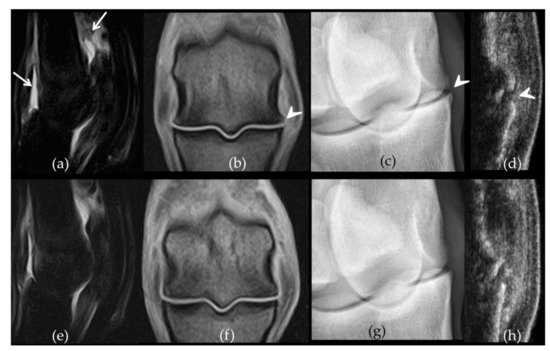

2.2. Follow-Up with Imaging Techniques